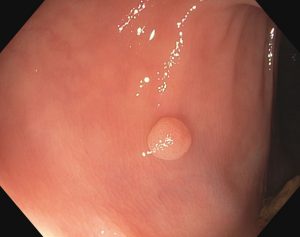

Ο πολύποδας είναι μία μάζα κυττάρων,ένα μικρό εξόγκωμα, της εσωτερικής επένδυσης του παχέος εντέρου .Ένας πολύποδας σε σχέση με την εσωτερική επιφάνεια του εντέρου μπορεί να είναι επίπεδος ή ανυψωμένος. Υπάρχουν διάφοροι τύποι πολυπόδων, και μερικοί μπορούν τελικά να αναπτυχθούν με την πάροδο του χρόνου και να γίνουν καρκίνος.

Κολονοσκόπηση: Μια διαδικασία κατά την οποία ένας μακρύς, λεπτός, εύκαμπτος σωλήνας τοποθετείται από τον πρωκτό μέσα στο παχύ έντερο. Ο σωλήνας διαθέτει μια κάμερα που δείχνει εικόνες σε μια οθόνη και ένα εργαλείο για να κόψει τυχόν πολύποδες.